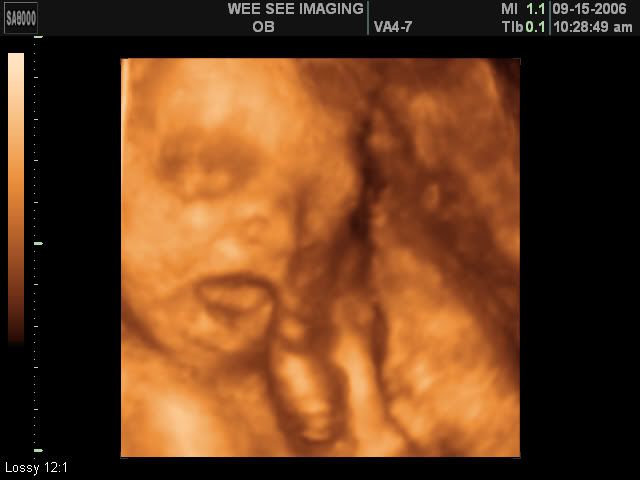

Victoria Rose Kelly

Date Due: December 15, 2006